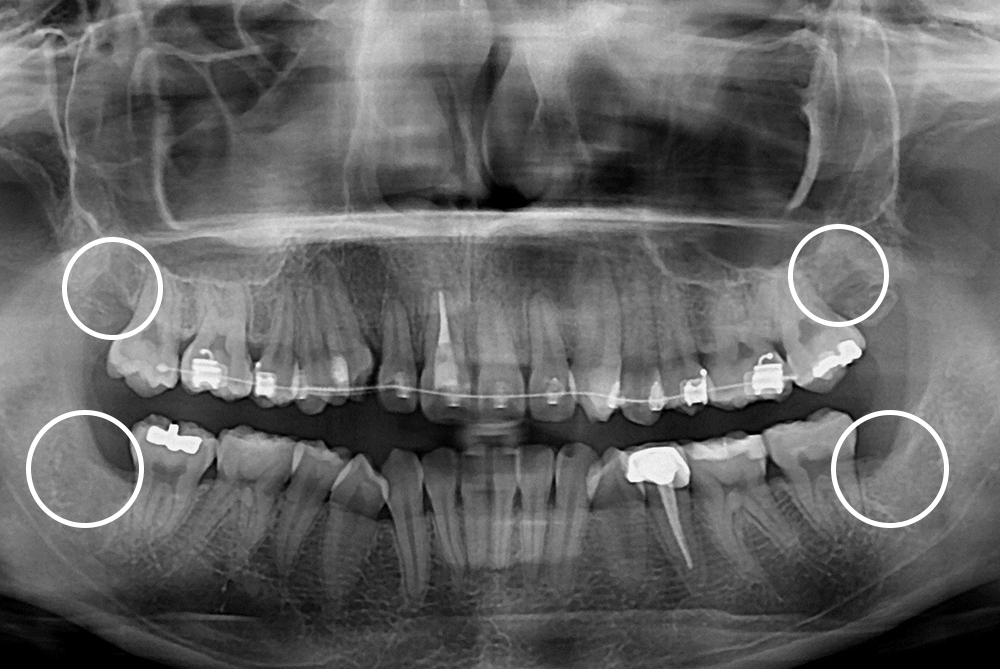

[사랑니] 매복 사랑니 발치

치료후 : 2019-06-12

세종치과는 구강악안면외과학 박사이신 원장님이 발치하는 치과입니다.